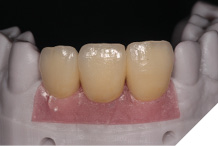

The definitive metal ceramic bridge was fabricated with the new soft tissue emergence profiles. The framework was fabricated by Creates and due to the short nature of the span we felt the intraoral scan was sufficiently accurate without the need for a verification jig to ensure passive framework fit into the implant fixtures. The ceramic work was optimally shaped for cleans ability and long-term soft tissue adherence and maintenance.

The definitive bridge was fitted and torqued in situ uneventfully after such excellent healing of the provisional bridge (Figs. 31-37).